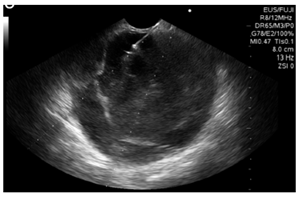

Se realizó una ultrasonografía endoscópica (EUS) biliopancreática que mostró una masa sólido-quística de 60 x 60 mm en la cola del páncreas, con un grosor de la pared de 4 mm, ecogenicidad mixta, sin componente vascular ni calcificaciones; y la presencia de una lesión de aspecto polipoide en su interior de 30 mm (Figura 2). Se realizó una punción con aguja fina (FNA) con aguja n.° 19 G (Wilson Cook) (Figura 3) y se obtuvieron 4 cc de líquido mucoide con múltiples fragmentos blanco-amarillos, para el procesamiento de citología y bloque celular. La coloración hematoxilina-eosina mostró células epiteliales escamosas y mononucleares, tejido necrótico, hemorragia reciente y antigua con escasas células glandulares sin atipia. No había evidencia de tejido pancreático. El procesamiento del ACE no se realizó porque no había disponibilidad de dicho recurso en la institución.

La EUS-FNA, realizada mediante el uso de un ecoendoscopio lineal desde el duodeno o el estómago, permite obtener material citológico en tiempo real de manera segura a través del uso de agujas de 19 o 22 Gauges, dirigidas hacia la luz del quiste. Lo ideal es hacer la punción en un solo paso, aspirando el contenido hasta lograr el colapso del quiste y, de este modo, prevenir complicaciones infecciosas. Debe tomarse biopsia de los nódulos, septos, y masas adyacentes asociadas. Se debe administrar una dosis de antibiótico profiláctico y durante 3 a 5 días después de la punción para prevenir la infección 13.

El tamaño y la localización no son predictores de la aspiración exitosa del quiste. 1,5 cm es el tamaño requerido como mínimo para lograr tasas de éxito del 85% 15. Esta herramienta facilita la evaluación de algunas características en el fluido del quiste, tales como la viscosidad, la citología, la química, marcadores tumorales y técnicas de análisis molecular.